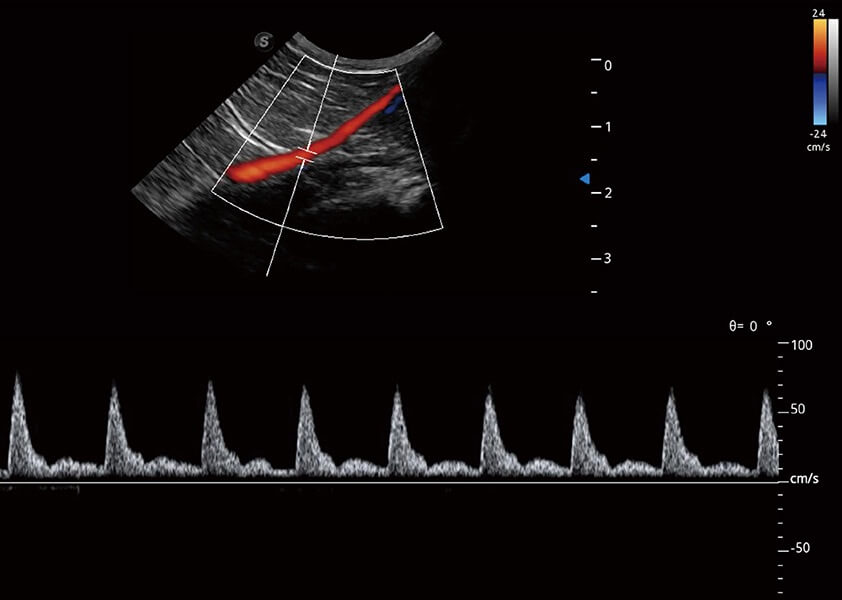

(猫)髂动脉血流频谱

4T血流成像 微察秋毫

融合不同血流成像技术的优势,即可以提升血流成束性,同时可提高血流的视觉敏感性。